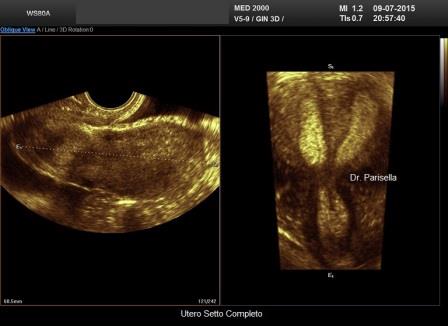

Utero Setto

E' la malformazione uterina più frequente (55% delle anomalie mulleriane); è la conseguenza di un incompleto riassorbimento del setto uterovaginale dopo la fusione dei dotti di Muller.

Ecograficamente è fondamentale la visualizzazione del profilo del fondo uterino per differenziarlo dall'utero bicorne. Nell'utero setto il profilo del fondo può essere convesso, appianato o a volte concavo. L'eco 3D, permettendo una accurata scansione coronale consente, nella maggior parte dei casi, di poter differenziare questa anomalia dall'utero bicorne.

Si distinguono due tipi di utero setto:

- utero setto completo: il setto si estende dal fondo alla cervice

- utero setto incompleto: il setto origina dal fondo e non giunge all'OUI.

L'Utero setto può associarsi a varie complicanze ostetriche:

- aborti nel I e nel II trimestre

- parti pretermine

- anomalie di posizione fetale

- ritardo di crescita fetale

L'utero setto è facilmente correggibile per via isteroscopica.